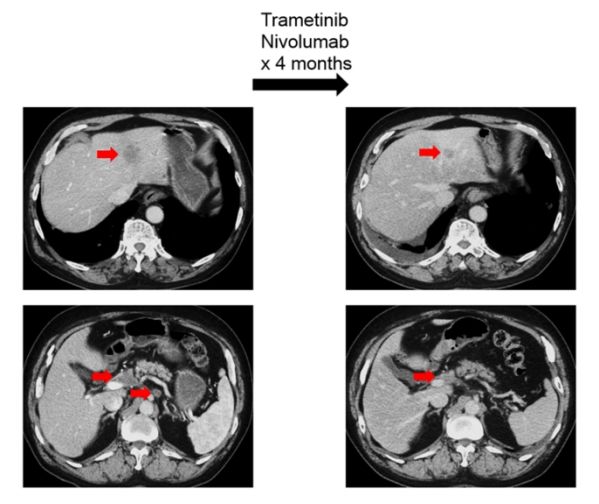

图4患者接受MEK抑制剂及其他靶向治疗案例

因此靶向RAS突变的药物,如MEK抑制剂可能会因大量共突变导致耐药,研究中观察到,RAS突变的多数患者携带的基因共突变可能起到了很重要的致癌作用(图1),因此如要有效的靶向抑制RAS可能需要同时抑制MEK通路及每个患者特异性的共出现的致癌突变。本研究证实,同时应用MEK抑制剂联合靶向匹配的共突变靶向药物可获得33%的客观缓解率,本研究中一例胰腺癌携带KRAS和CDKN2A突变,给予曲美替尼和哌柏西利治疗,部分缓解疗效维持了9个月,该患曾既往接受过含哌柏西利的治疗失败,但当时该方案中未包括MEK抑制剂,提示临床阶段这种治疗方式值得进一步探索。